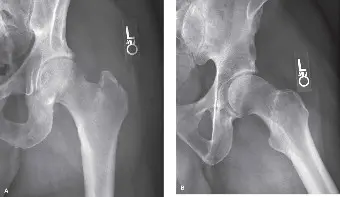

صورة توضح كسرًا بين المدورين مفتتًا مع إزاحة كبيرة. يُظهر الرد غير الأمثل، مثل التقوس المتبقي أو عدم استعادة الدعامة الخلفية الإنسية بشكل كافٍ، زيادة خطر فشل الغرسة بشكل كبير. -